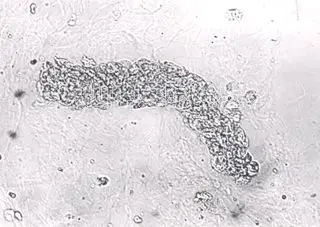

实验诊断学 红细胞管型

背景中可见较多的因染色而溶血的红细胞.